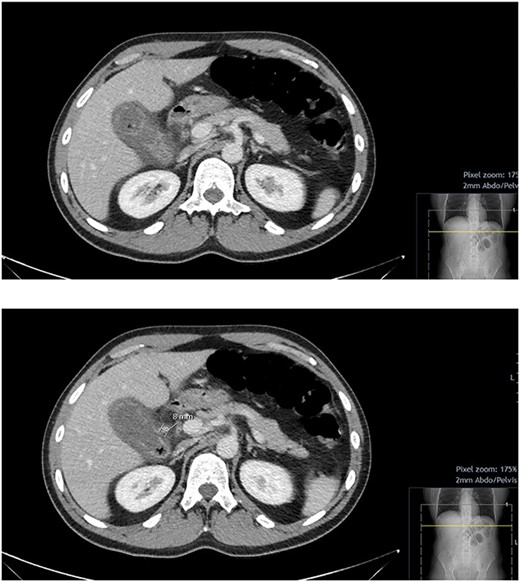

On initial blood tests, he had a raised inflammatory markers (C-reactive protein: 201 mg/l, white cell count: 16.2x109/l), a slightly raised ALP (99 IU/l) however all other blood results were unremarkable. He underwent a computed tomography (CT) abdomen pelvis with contrast, which showed a picture of acute calculous cholecystitis with oedematous walls and air within the walls and the gallbladder itself, raising a suspicion of EC. Incidentally, a 7.6-mm pseudoaneurysm was noted at the level of the anterior branch of the cystic artery (Figs 1 and 2).

CT abdomen and pelvis with contrast; hyper-enhancing, oedematous gallbladder wall with fat stranding and gas locules consistent with acute calculous cholecystitis; suspected pseudoaneurysm of the cystic artery measuring 7.6 mm.